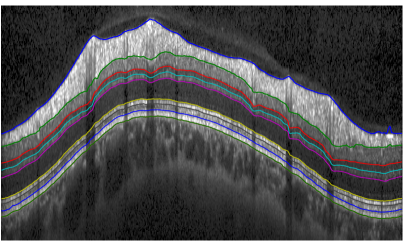

To our knowledge this is the only work, where a full global shape prior is employed for the task of OCT retina segmentation. Moreover, we are not aware of any other segmentation approach that infers a full probability distribution. Our approach offers excellent segmentation performance, outperforming approaches relying on local or no shape regularization, as well as pathology detection and an assessment of segmentation quality. Fig. 1 illustrates the segmented boundaries, but additional boundaries like the external limiting membrane (ELM) could easily be incorporated if ground truth is available.

Refer to caption

Figure 1: Overview of retinal layers segmented by our approach and their corresponding anatomical names. The used abbreviations correspond to nerve fibre layer (NFL), ganglion cell layer and inner plexiform layer (GCL + IPL), inner nuclear layer (INL), outer plexiform layer (OPL), outer nuclear layer and inner segment (ONL + IS), connecting cilia (CC), outer segment (OS), retinal pigment epithelium (RPE).